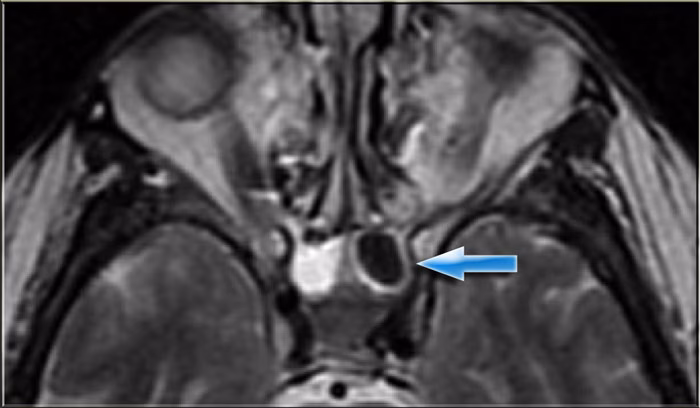

MR-scanning af bihulerne: Detaljeret kig uden stråling

En MR-scanning (Magnetisk Resonans) er en avanceret, ikke-invasiv billeddannelsesteknik, der bruger kraftige magneter og radiobølger til at skabe ekstremt detaljerede billeder af kroppens indre. En af de største fordele ved en MR-scanning er dens uovertrufne evne til at vise bløddele som slimhinder, muskler og eventuelle unormale vækster.

- Vurdere komplicerede svampeinfektioner: Visse typer svampeinfektioner ses bedst på en MR-scanning.

- Opdage spredning af infektion: Hvis der er mistanke om, at en infektion har spredt sig til øjenhulen eller hjernen, er MR det foretrukne værktøj.

Hvordan ser en scanning ud? Tolkning af billeder

Når en radiolog ser på dine scanningsbilleder, leder de efter afvigelser fra det normale. Sunde bihuler fremstår som mørke, luftfyldte rum på en CT-scanning, omgivet af tynde, hvide knoglevægge. Tegn på problemer kan omfatte:

- Fortykket slimhinde: Ved kronisk bihulebetændelse bliver slimhinden betændt og hævet, hvilket ses som et gråt lag langs indersiden af bihulevæggen.

- Væskeansamling (fortætning): Hvis en bihule er helt blokeret og fyldt med væske eller slim, vil den se hvid eller grå ud på scanningen.

- Polypper: Disse fremstår som bløde, grålige, drueklase-lignende masser, der kan fylde næsehulen eller bihulerne.